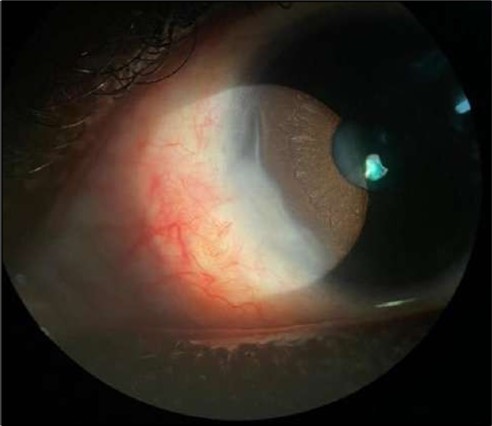

On the current presentation, Snellen VA was 6/6 in the right eye and 6/9 in the left eye, with normal IOP. The left eye demonstrated mild upper lid edema and intense nasal ciliary injection. Slit-lamp evaluation revealed a crescentic area of stromal corneal melting between 7 and 10 o’clock nasally, with overhanging edges and a fluorescein-positive base. No corneal infiltrates were present, and the surrounding stroma remained clear. The anterior chamber was deep and quiet, lens was transparent, pupil was round and reactive & normal posterior segment. Anterior segment optical coherence tomography (AS-OCT) confirmed a localized ulcer, measuring 1324 µm in horizontal width and extending to a depth of 380 μm, compared with an adjacent healthy corneal thickness of 824 µm, corresponding to approximately 46.1% stromal thinning (Figure 1a, Figure 1b, Figure 1c)

Figure 1a.Left eye (OS), on presentation. Slit-lamp image: crescent-shaped peripheral corneal ulceration located nasally, with severe adjacent conjunctival injection, peripheral thinning, and stromal infiltration.

Despite systemic and topical management over one month, the epithelial defect persisted, indicating refractoriness to medical therapy. OCT imaging showed ulcer depth reduction to nearly 42% stromal thinning and width of 1180 µm, highlighting partial corneal healing. In view of the persistent ulcer and ongoing local inflammation, a conjunctival resection was performed to excise the perilimbal inflammatory focus and promote corneal repair Figure 3a and 3b.

Figure 4.OS. Slit-lamp photograph showing a partially quiet ocular surface two weeks following surgical excision of adjacent perilimbal conjunctiva.

Figure 6.Six-month follow-up image showing a stable ocular surface, and absence of ulcer recurrence. The cornea appears clear centrally, with stromal scarring limited to the periphery.